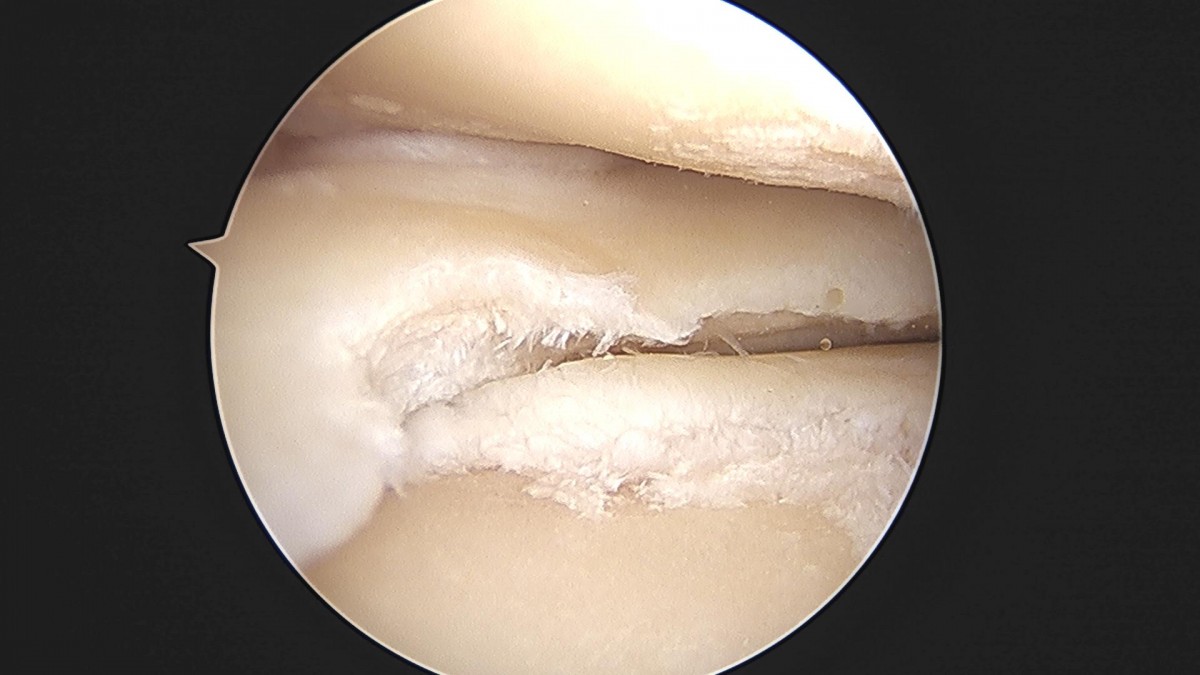

배우한원장님 무릎 반월상연골판 절제술 최갑O 환자

ade708f6ffdfd2e6dcf188e7ecb45ff3_1673514068_5784.jpg